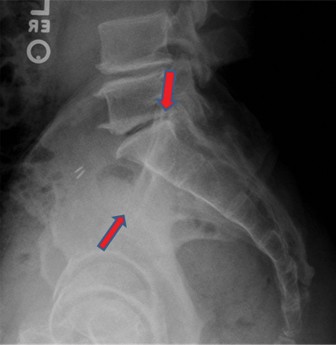

You are the sole provider in a small rural hospital when a 56-year-old female is brought in after a MVC rollo…